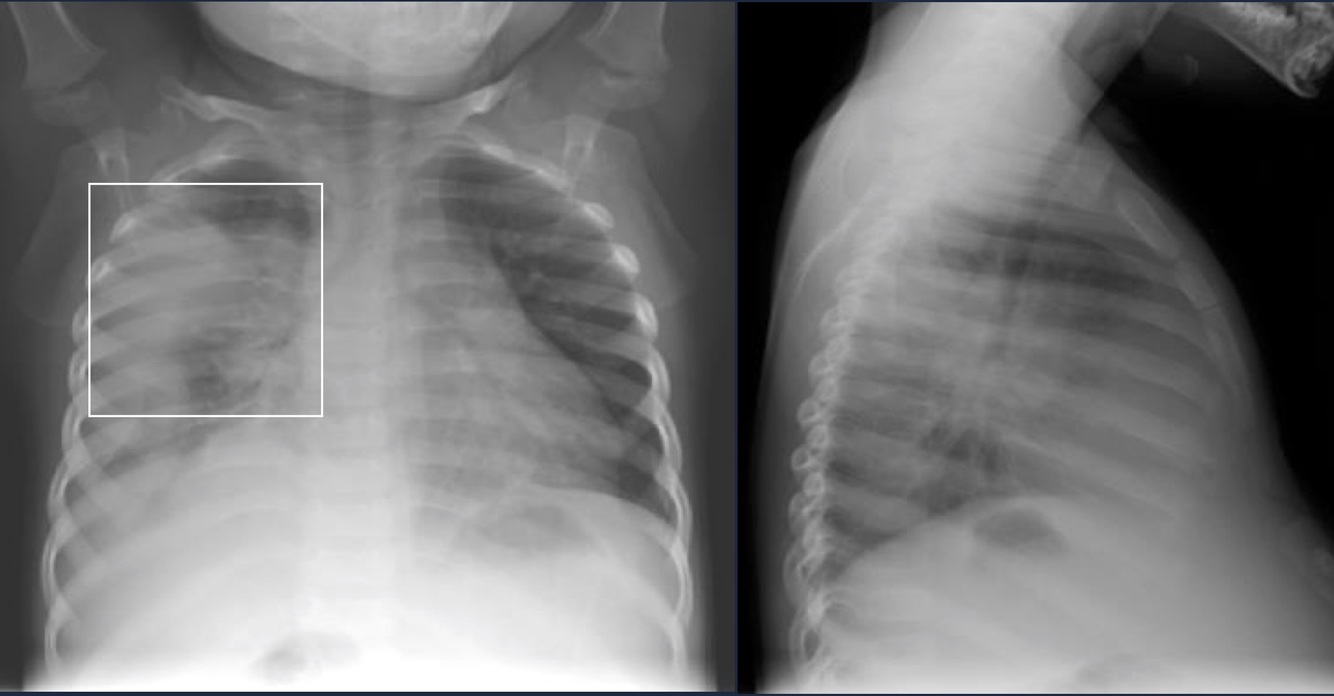

CXR: Complicated PNA with pleural involvement.

Empyema

Pus within the pleural cavity.